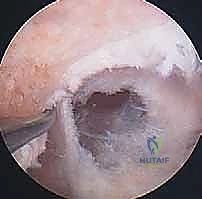

الخطوة الأولى: الفحص بالمنظار الجراحي 4K

يستخدم الدكتور